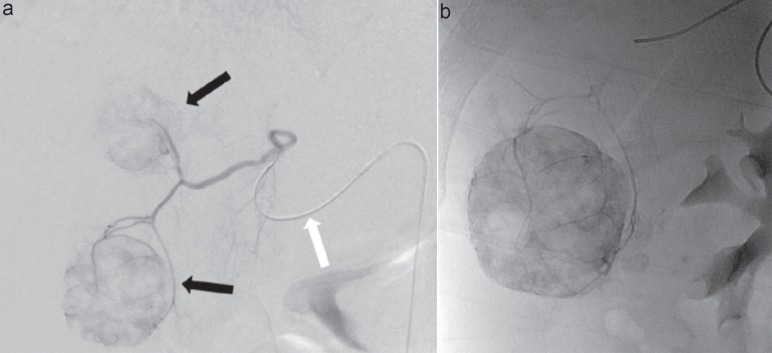

Abstract Image